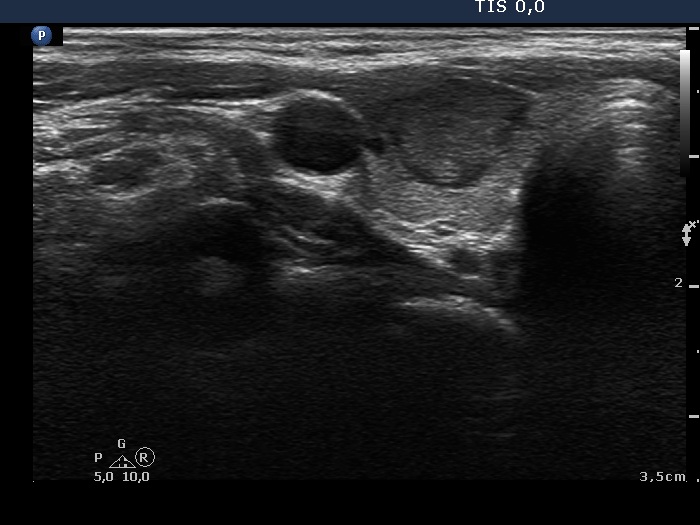

First examination (first row of images)

Clinical data: A 21-year-old woman was referred for evaluation on a nodular goiter. She has noticed an enlargement in the left lobe for a year. On evaluation in another institute, a cystic nodule was diagnosed with a 26 mm maximal diameter and 3 mL brown fluid was aspirated. Cytology resulted in benign cystic lesion.

Palpation: The right lobe was suspicious having a nodule.

Laboratory test: TSH 2.21 mIU/L.

Ultrasonography. The thyroid was echonormal and presented a moderately hypoechoic nodule in the right lobe and a cystic nodule with minimally hypoechoic solid part corresponding to the previously aspirated cystic lesion. The largest diameter of the latter was 11 mm which means that cyst has not refilled. The nodule in the right lobe showed irregular, more hypoechoic areas all along at the periphery. This pattern mimicked halo sign, but indeed the lesion did not have a real halo. The vascularization of the nodule in the right lobe presented an irregularly increased intranodular blood flow while the lesion in the left lobe did signs of perinodular vascularization.

Cytology was performed form the lesion in the right lobe and resulted in follicular proliferation.

Combined ultrasound-cytological diagnosis was benign follicular proliferation.

Suggestion: ultrasound in a year.